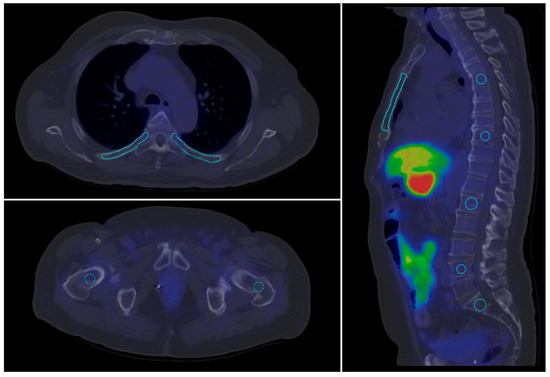

4.3. Imaging Analysis

For the quantitative evaluation of tracer uptake on PET and SPECT slices, target volumes of interest (VOIs) were defined using a semi-automated method, excluding any visible abnormalities on the corresponding CT slices. The VOI segmentation were performed in InterViewTM FUSION software (Mediso Medical Imaging Systems Ltd., Budapest, Hungary).To assess healthy bone uptake, 10 different bone contours were outlined at predefined, standard locations. Healthy parotid gland, aortic arch (blood pool), liver and spleen tissues were selected as reference regions. VOIs were defined on both SPECT and PET scans in areas without visible abnormalities on CT slices (see Table 3). A visual representation of this process is shown in Figure 6.

Figure 6. Contoured skeletal volumes of interest (VOI) (blue lines) in standard locations on a [18F]F-JK-PSMA PET/CT scan.